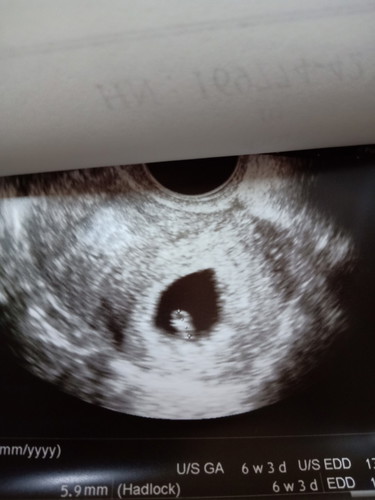

ภาพนี้คือตอนอัลตราซาวด์ตอน 6 สัปดาห์ค่ะ ตอนนั้นยังเห็นเเต่ถุงไข่แดง ยังไม่ได้ยินการเต้นของหัวใจ ได้ยินการเต้นของหัวใจลูกตอนคุณหมอนัด 8 สัปดาห์ค่ะ

จากที่แม่บ้านนี้ ไปฝากครรภ์ และอัลตร้าซาวด์ผ่านหน้าท้อง เห็นแค่ถุงการตั้งครรภ์แต่ไม่เห็นตัวเด็ก วันนี้ไปอัลตร้าซาวด์ผ่านช่องคลอดมาค่ะ เห็นตัวเด็กแล้วค่ะ แต่ที่น่ากังวลคือ หมอไม่เห็นการเต้นของหัวใจเด็ก ซึ่งอาจเป็นไปได้ว่าอายุครรภ์ยังน้อย หรือไม่ลูกอาจไม่อยู่กับเราแล้ว ตอนแรกคุณแม่คาดประจำเดือนครั้งสุดท้ายคลาดเคลื่อน อัลตร้าซาวด์วันนี้ หมอบอกว่าอายุครรภ์ 6 สัปดาห์ ค่ะ ขอคำแนะนำจากคุณแม่ที่มีประสบการณ์ค่ะ คุณแม่บ้านไหนเคยมีประสบการณ์ลูกมองไม่เห็นการเต้นของหัวใจค่ะ กังวลมาก

6 สัปดาห์ ตัวอ่อนยังเล็กมากค่ะ เป็นไปได้ที่จะยังไม่เห็นรายละเอียดนัก ไม่อยากให้เครียดเลยค่ะ เพราะความเครียดส่งผลเสียหลายอย่าง พยายามทำใจให้สบาย บำรุงตัวเองให้ดี กินโฟลิคทุกวัน นอนหลับพักผ่อนเยอะๆนะคะ